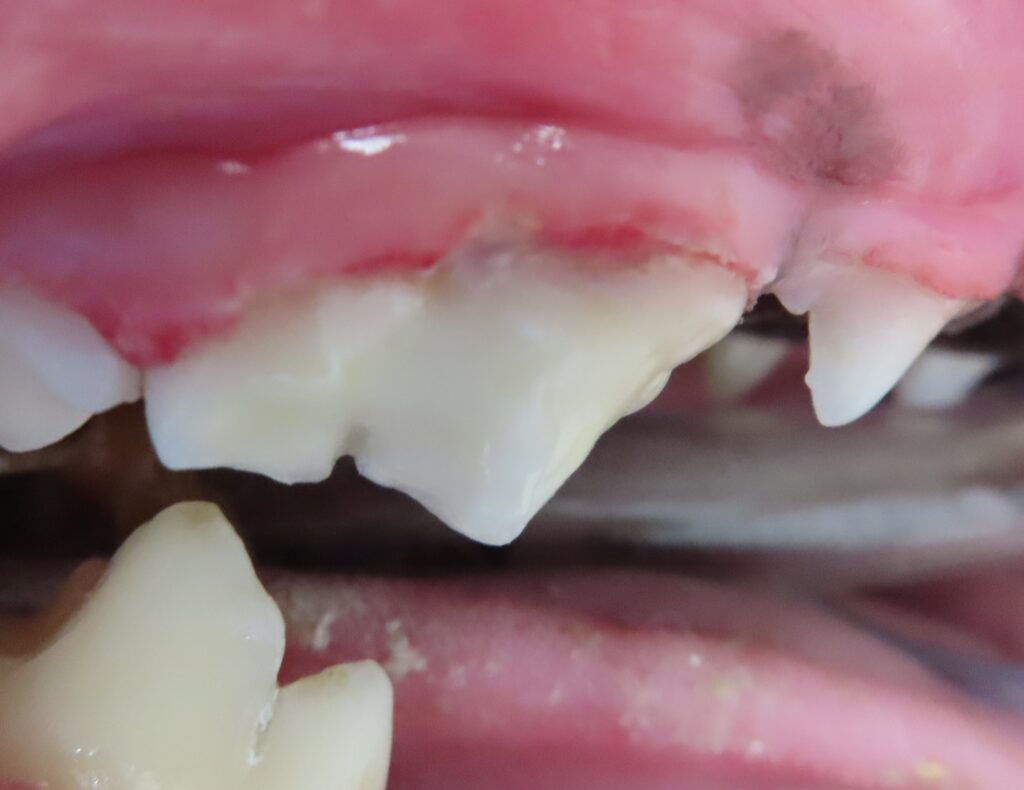

3.歯冠修復

最後に歯と同じ色の最終充填剤(コンポジットレジン)を充填して完成です。外見的に正常とほとんど変わらない歯になりました。